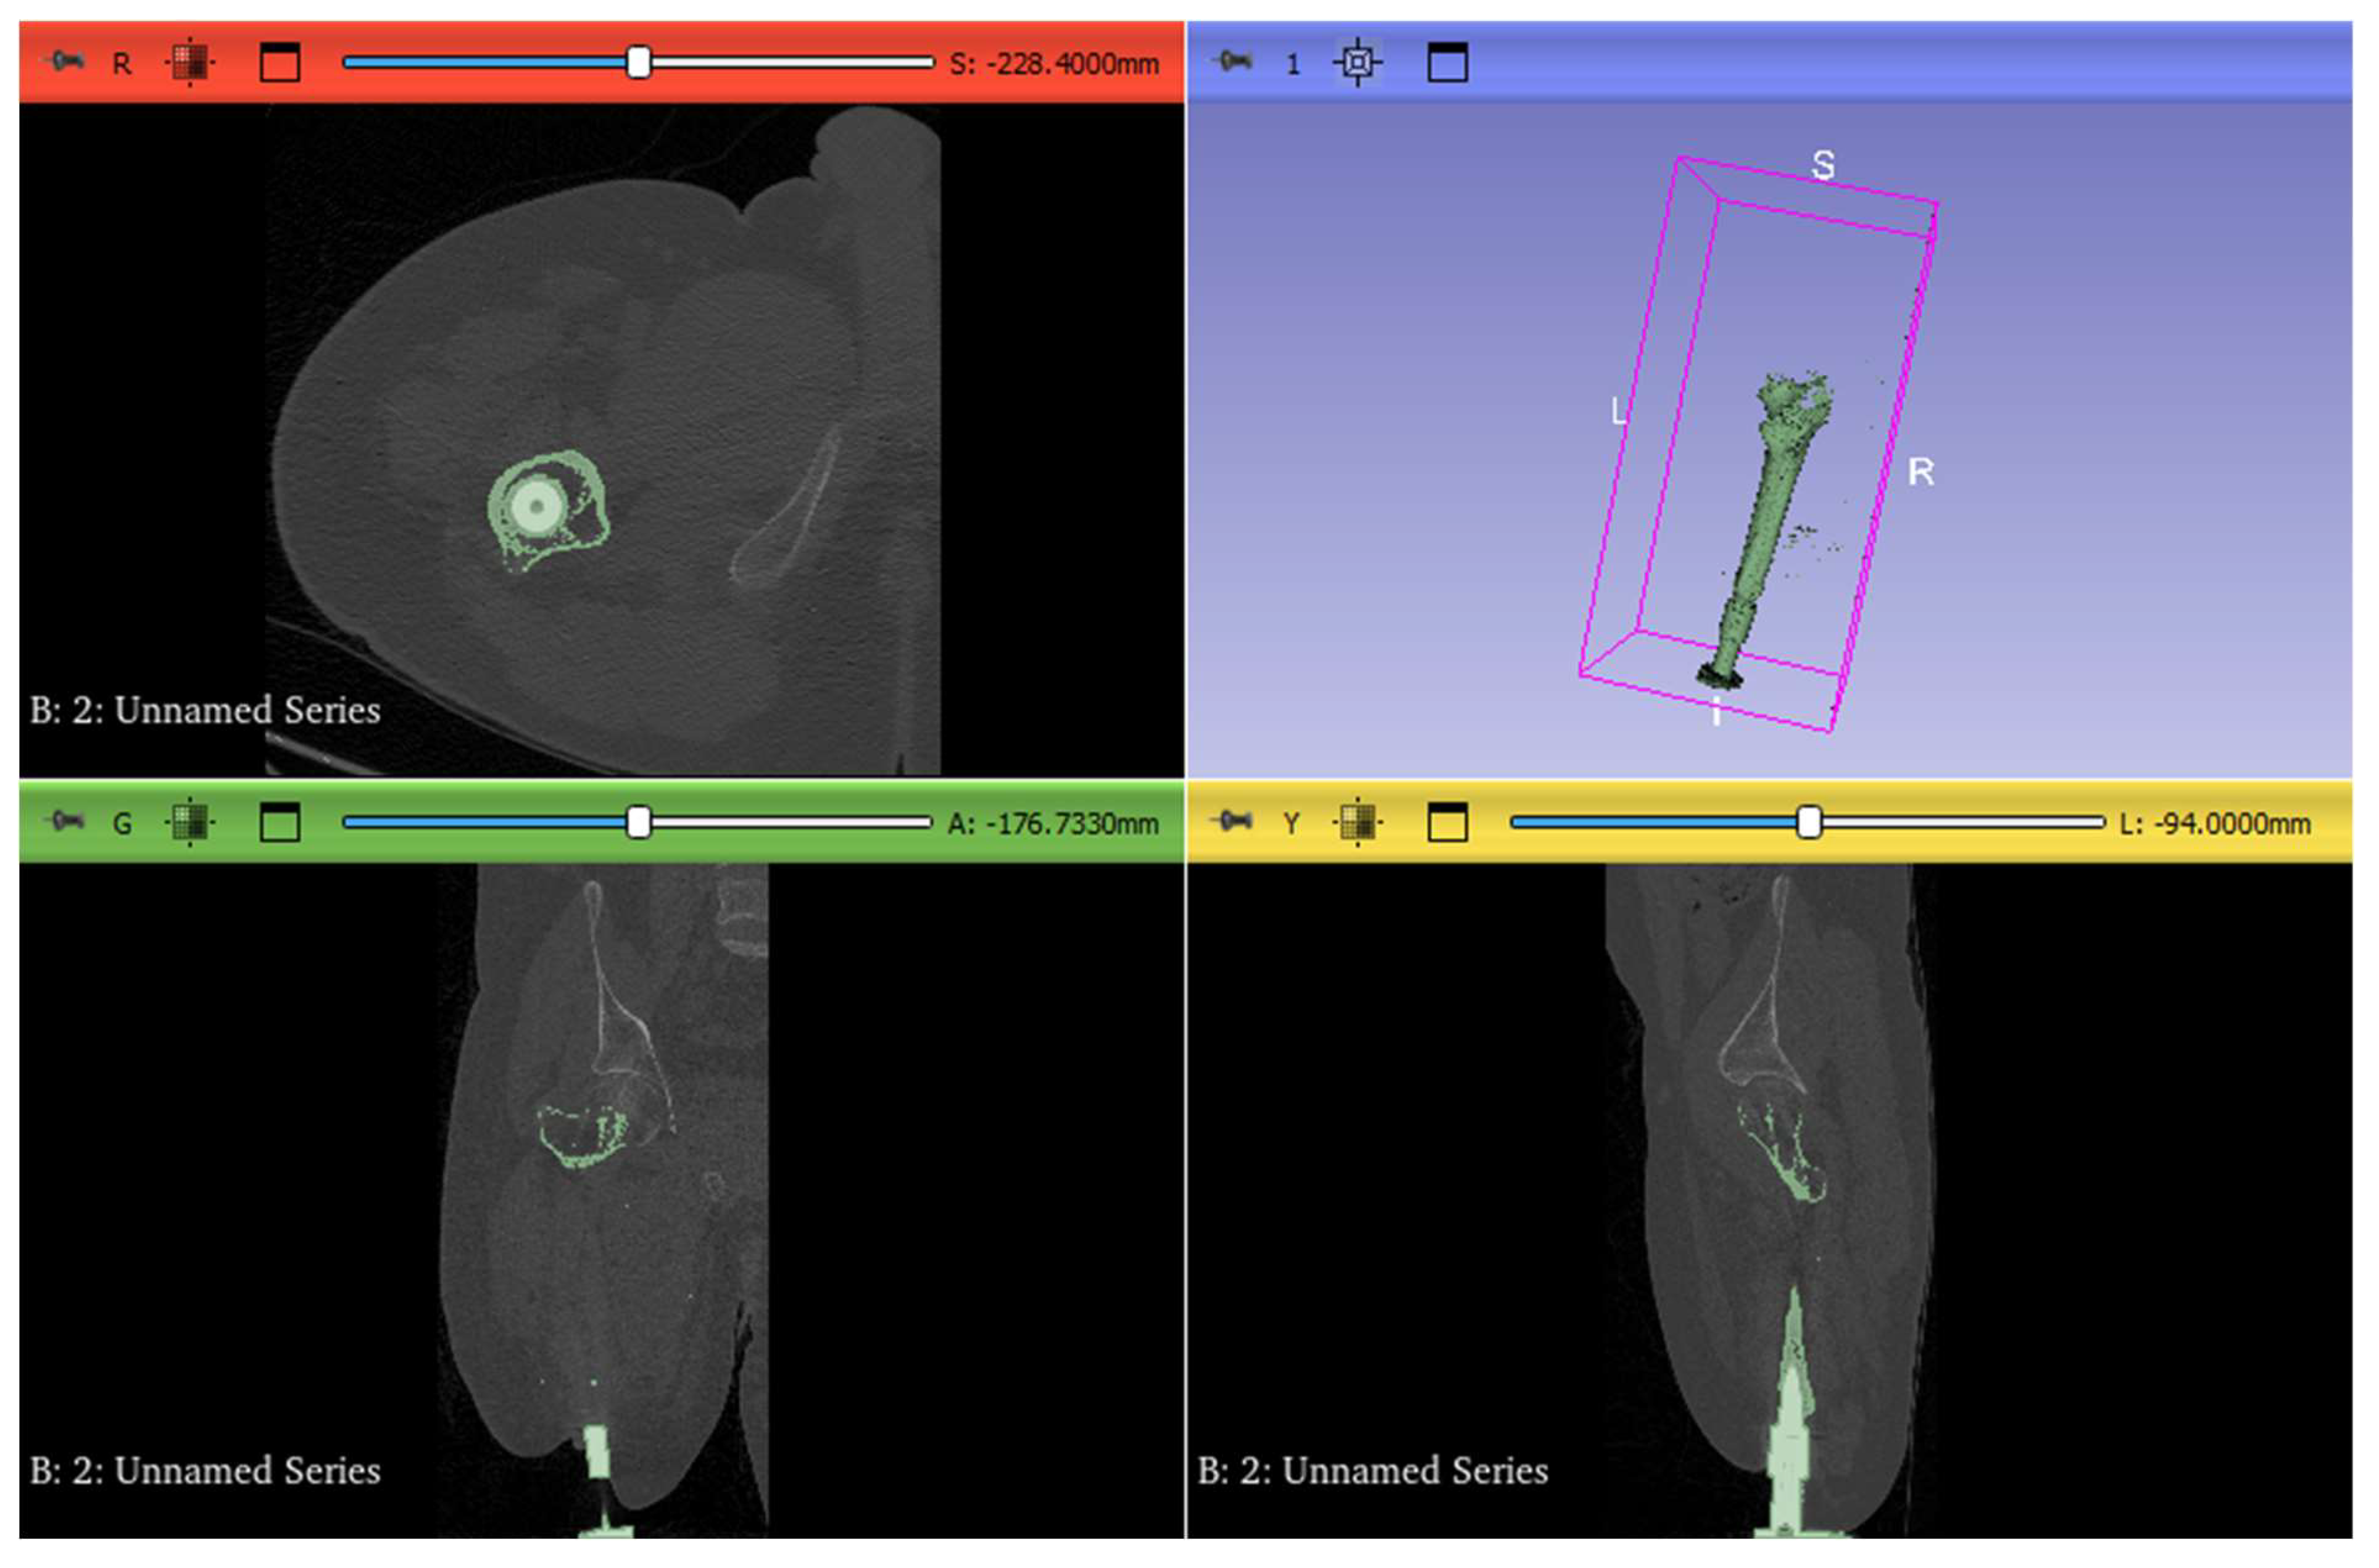

2. Experimental Works

3.1. CAD Model